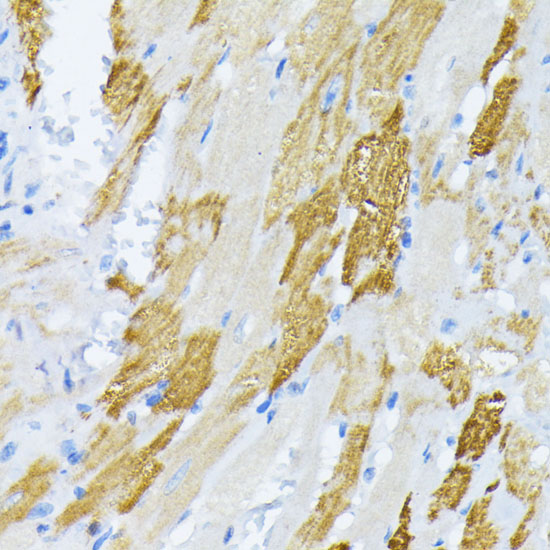

ApplicationWB, IHC